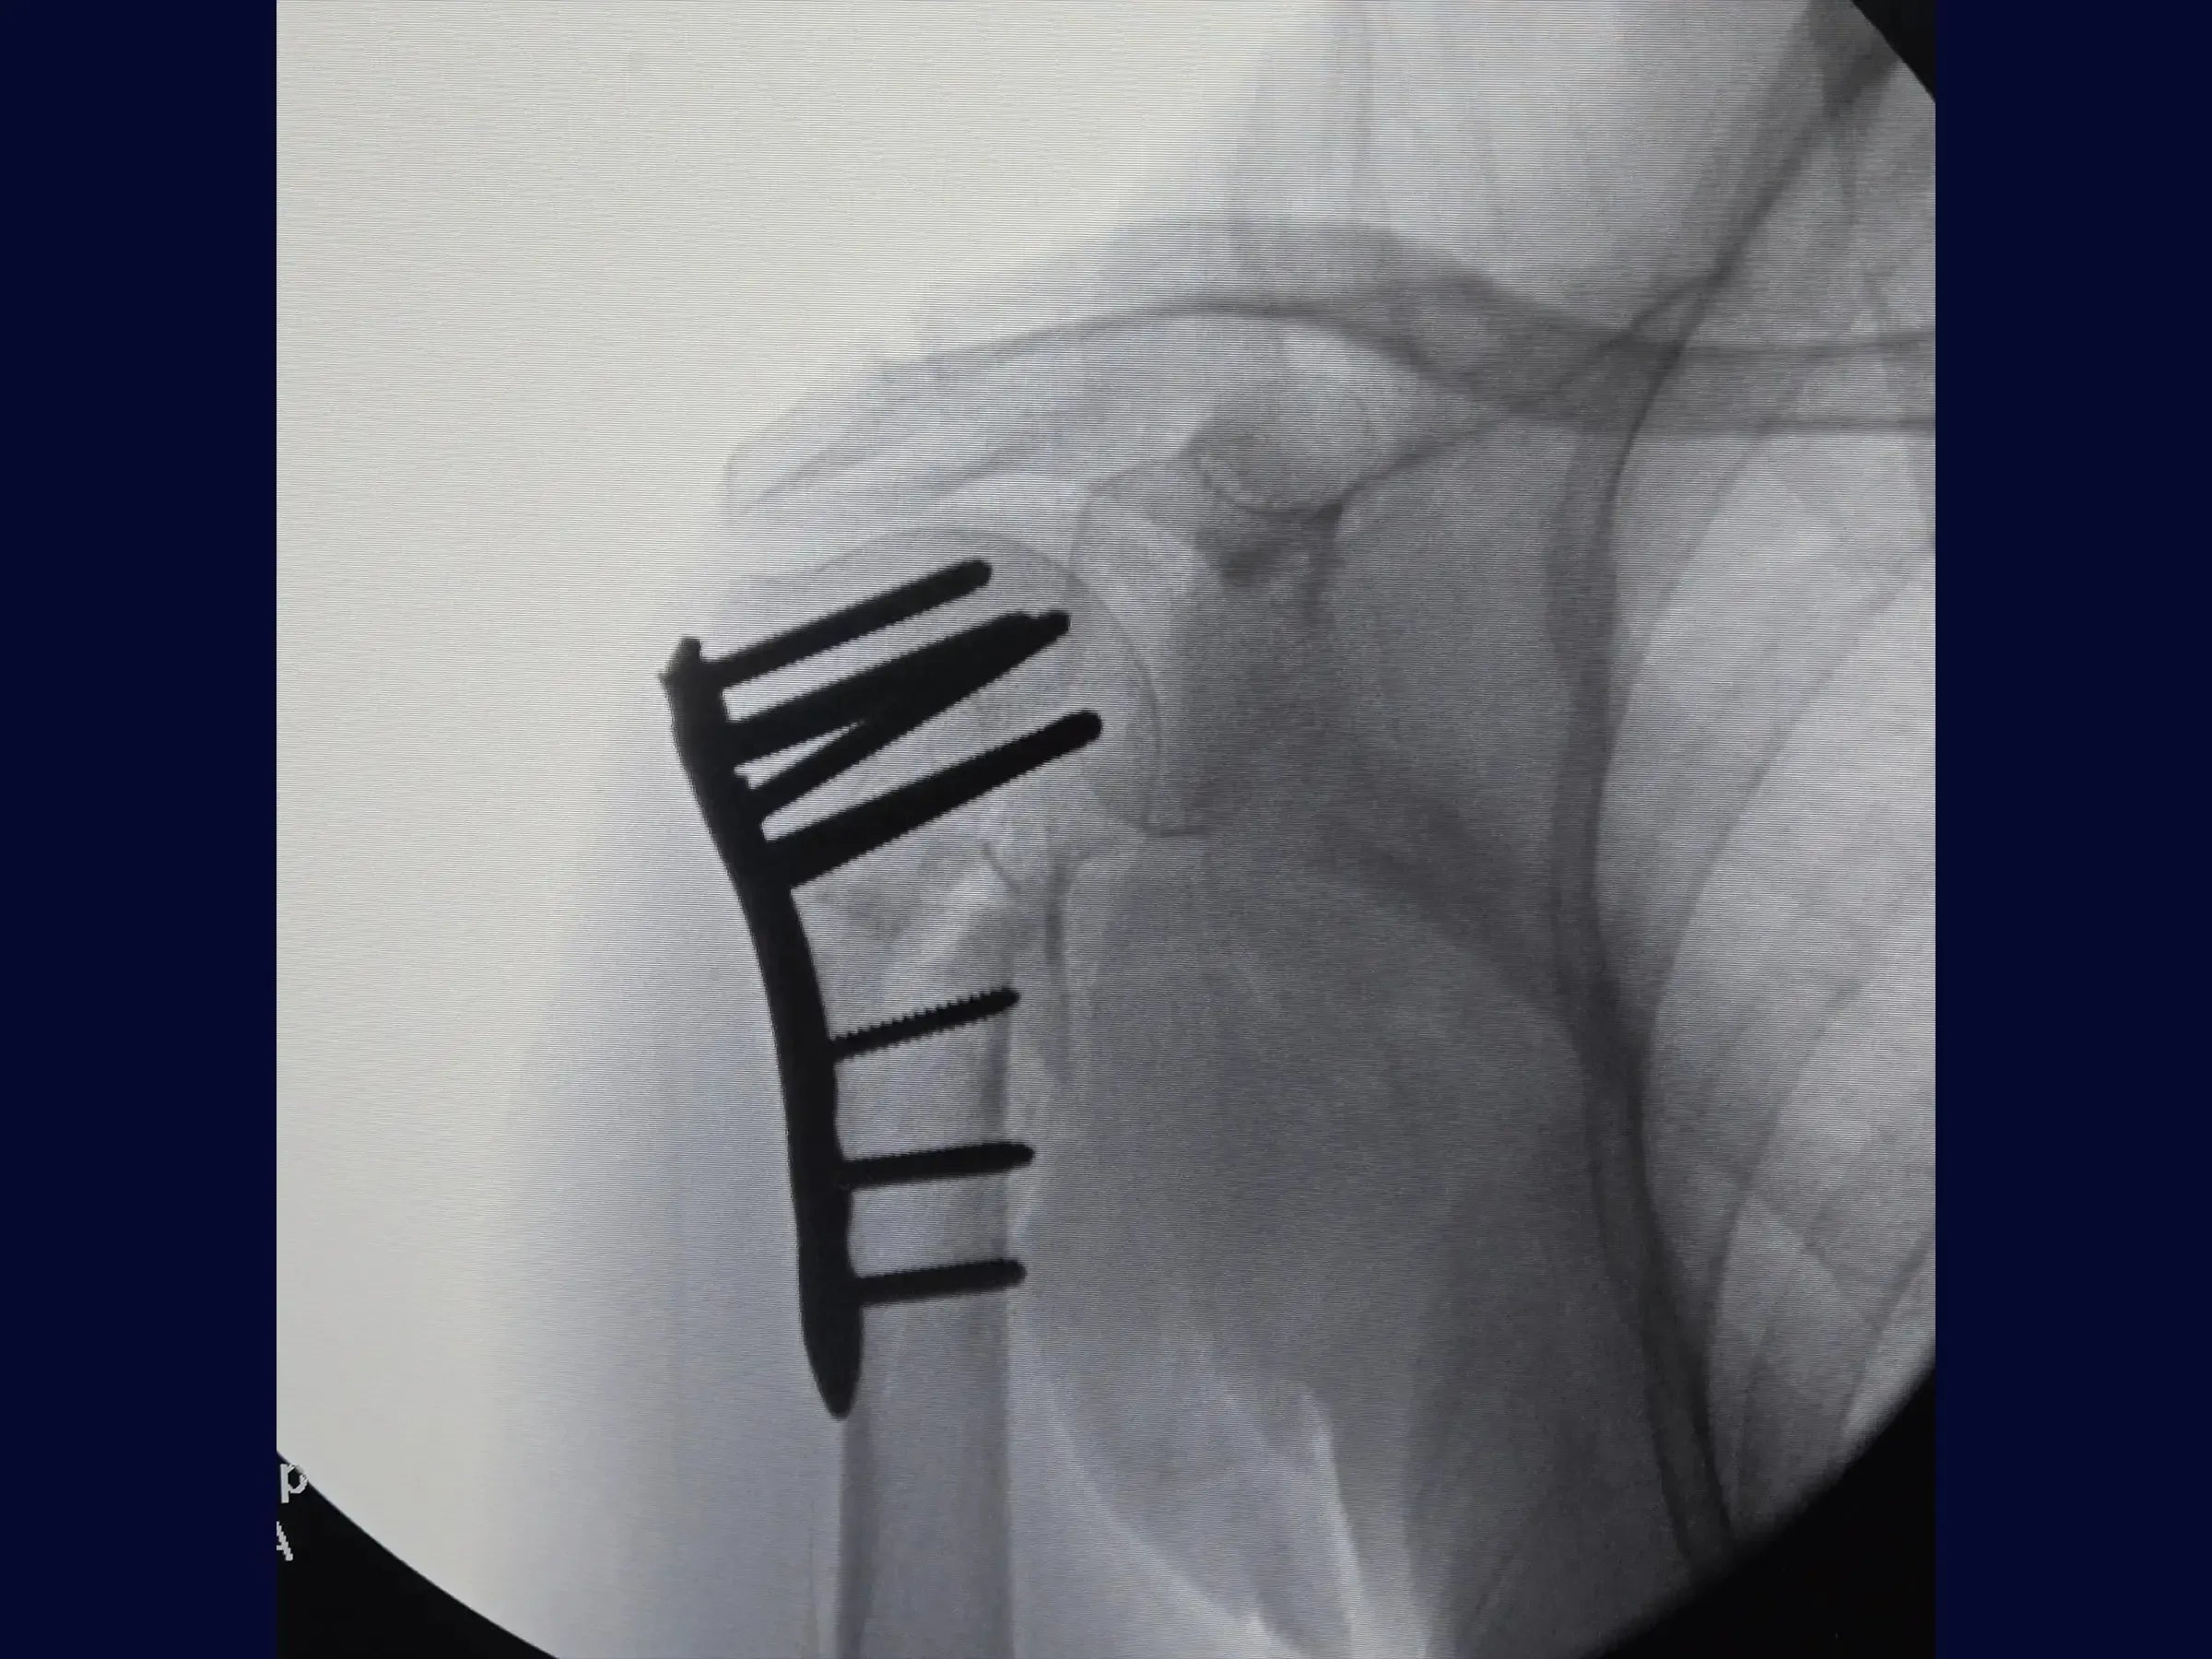

Proximal Humerus Fracture in 2 Parts (Deltopectoral Approach)

Master the treatment of proximal humerus fractures in 2 parts. This training offers a technical immersion in the deltopectoral approach for osteosynthesis, presented in 4K video from the surgeon's perspective, detailing each step of the procedure to optimize results.

- Brocage technique and measurement of screws for definitive subchondral fixation.

- Secure Subchondral Fixation: Drilling methodology with sensitivity for precise positioning of screws in the subchondral bone, without perforating the cartilage, with initial insertion of the screws from the calcaneus.

- Post-Operative Stability: Demonstration of the rotator cuff repair to the plate for additional stabilization, especially in osteoporotic bones, and management of the long head of the biceps.